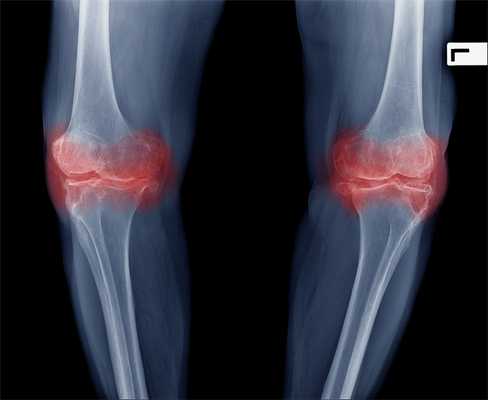

Артроз коленного сустава (гонартроз) — это прогрессирующее хроническое заболевание коленных суставов с повреждением, истончением и разрушением его хрящевой части (суставные поверхности бедренной и большеберцовой костей), а также поражением субхондральной кости. [2] [5] [16] Доказано исследованиями (артроскопия и МРТ), что помимо поражения суставного хряща в процесс вовлекаются мениски и синовиальная оболочка. Гонартроз — одна из самых распространенных ортопедических патологий. [4] [6] [9] [22] Существуют его синонимы — остеоартроз (ОА), деформирующий артроз. Заболевание является важной социально-экономической проблемой, так как широко распространено и значительно ухудшает качество жизни больных из-за постоянного болевого синдрома и, кроме того, становится причиной высокой инвалидизации. [15] [27]

До середины восьмидесятых годов прошлого века не было унифицированного определения заболевания. Только к 1995 году комитетом по остеоартрозу Американского колледжа ревматологии заболевание было охарактеризовано как результат действия механического и биологического факторов, приводящих к дисбалансу между процессами деградации и синтеза внеклеточного матрикса суставного хряща. [11] [19] В итоге происходит его разволокнение и дегенерация, образуются трещины, остеосклероз и уплотнение кортикального слоя субхондральной кости, растут остеофиты и формируются субхондральные кисты. [12] [29]

При артрозе (остеоартрозе) кроме прогрессивного разрушения хряща, потери его эластичности и амортизирующих свойств, в процесс постепенно вовлекаются кости. [7] [29] Под нагрузкой возникают заострения по краям (экзостозы), которые по ошибке считают "отложениями солей" — при классическом артрозе никакого отложения солей не происходит. Прогрессируя, артроз продолжает «съедать» хрящ. Затем деформируется кость, там происходит образование кист, поражаются все структуры сустава, и нога искривляется. [11] [17]

На второй стадии хрящевая прослойка резко истончается, а местами и вовсе отсутствует. [22] Появляются остеофиты по краям суставных поверхностей. Изменяются качественные и количественные характеристики синовиальной жидкости сустава — она становится гуще, более вязкой, что приводит к ухудшению питающих и смазывающих свойств. [14] [16] Боли более продолжительные и интенсивные, часто при движении появляется хруст. Отмечается незначительное или умеренное ограничение движений и небольшая деформация сустава. Прием анальгетиков помогает снять болевой синдром.

Отсутствие хряща на большинстве поражённых участков, выраженный склероз (уплотнение) кости, множество остеофитов и резкое сужение или отсутствие суставной щели. [8] [15] Боли практически постоянные, походка нарушена. Подвижность резко ограничена, заметна деформация сустава. Препараты НПВС, физиопроцедуры и другие стандартные методы лечения артроза коленного сустава неэффективны. [11]